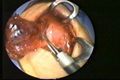

العمليات الجراحية التصويرية بالفيديو المنظاري

Videoendoskopik (Kapalı) Cerrahi

Paratiroidektomi

Tiroidektomi

Ameliyat'tan Görüntüler